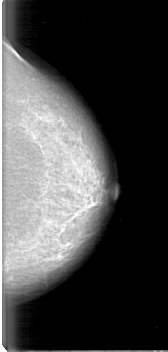

Digital Database for Screening Mammography

Volume: cancer_12 Case: D-4096-1

D_4096_1.LEFT_CC

LEFT_CC LINES 5266 PIXELS_PER_LINE 2506 BITS_PER_PIXEL 12 RESOLUTION 43.5 NON_OVERLAY

FILE: D_4096_1.RIGHT_CC.OVERLAY

TOTAL_ABNORMALITIES 1

ABNORMALITY 1

LESION_TYPE MASS SHAPE OVAL MARGINS OBSCURED

ASSESSMENT 0

SUBTLETY 5

PATHOLOGY MALIGNANT

TOTAL_OUTLINES 1

BOUNDARY